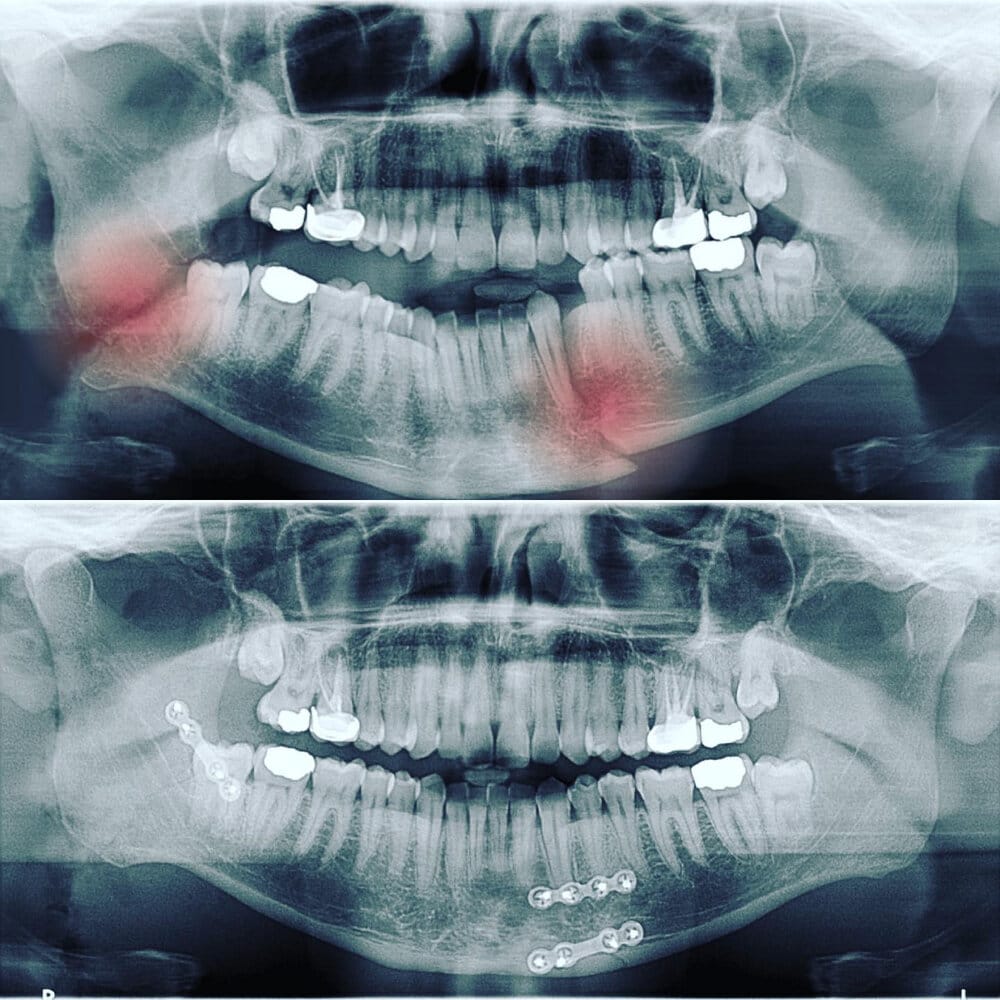

Appropriate diagnosis and a timely response will improve outcomes when managing traumatic dental injuries. Teeth can be broken during sports, games indoor or outdoor activity or fall in children and adults. Tooth may even come out of the socket (avulsion) or get deep into the socket (intrusion) during a fall or hit.

In many cases of traumatic dental injuries, the timeliness of care is key to saving the tooth. It is thus important for all dentists to have an understanding of how to diagnose and treat the most common dental injuries.